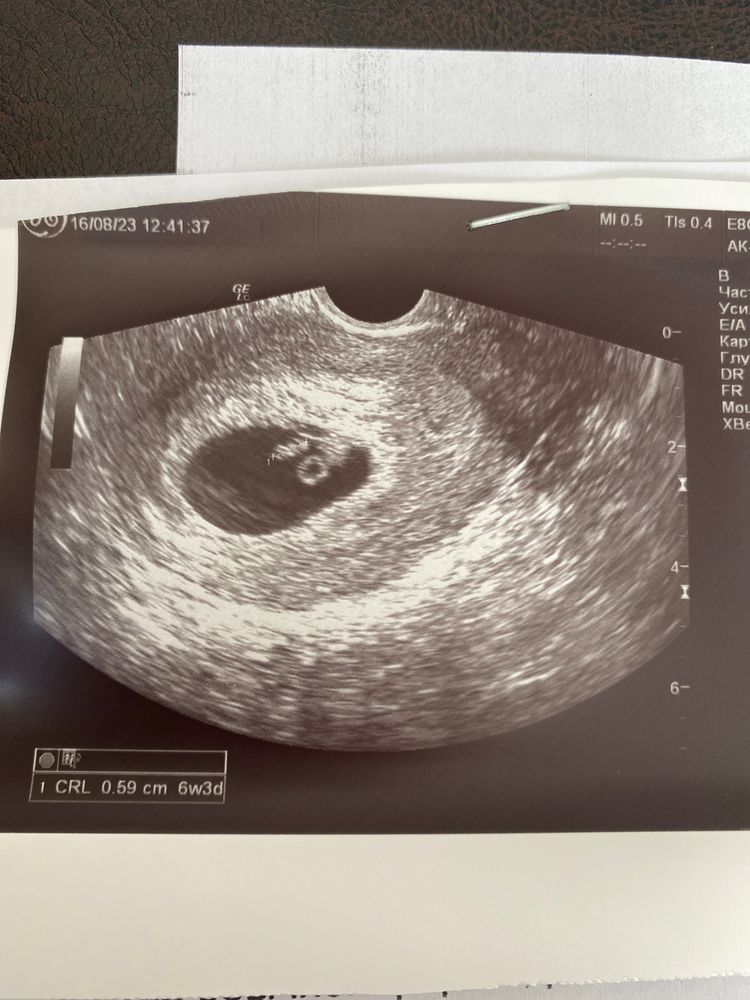

Сегодня мне прям показали мою креветочку 5,9мм и как пульсирует сердечко. Я расплакалась прям на кушетке! А сколько раз я сказала «спасибо» врачу, я и того не помню 😂

Видимо врач там что-то вообще перемудрила. На том узи желточный мешочек она увидела на 3,45мм, а здесь 1,8, такой же как был при самом первом узи.